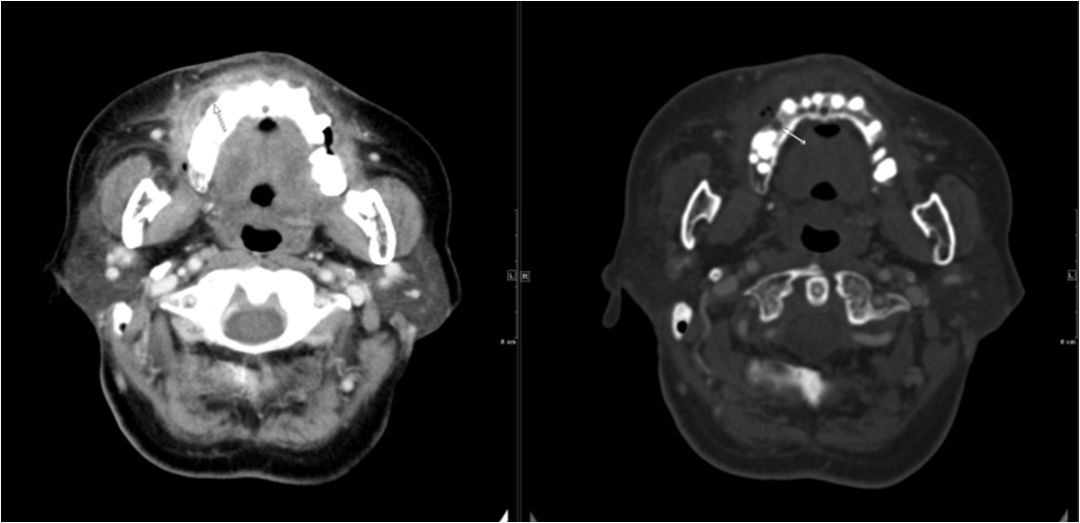

15 多间隙受累

(1)左下后牙疼痛11天余,颈部肿胀10天。

(2)右侧颌面部弥漫性肿胀1月余。